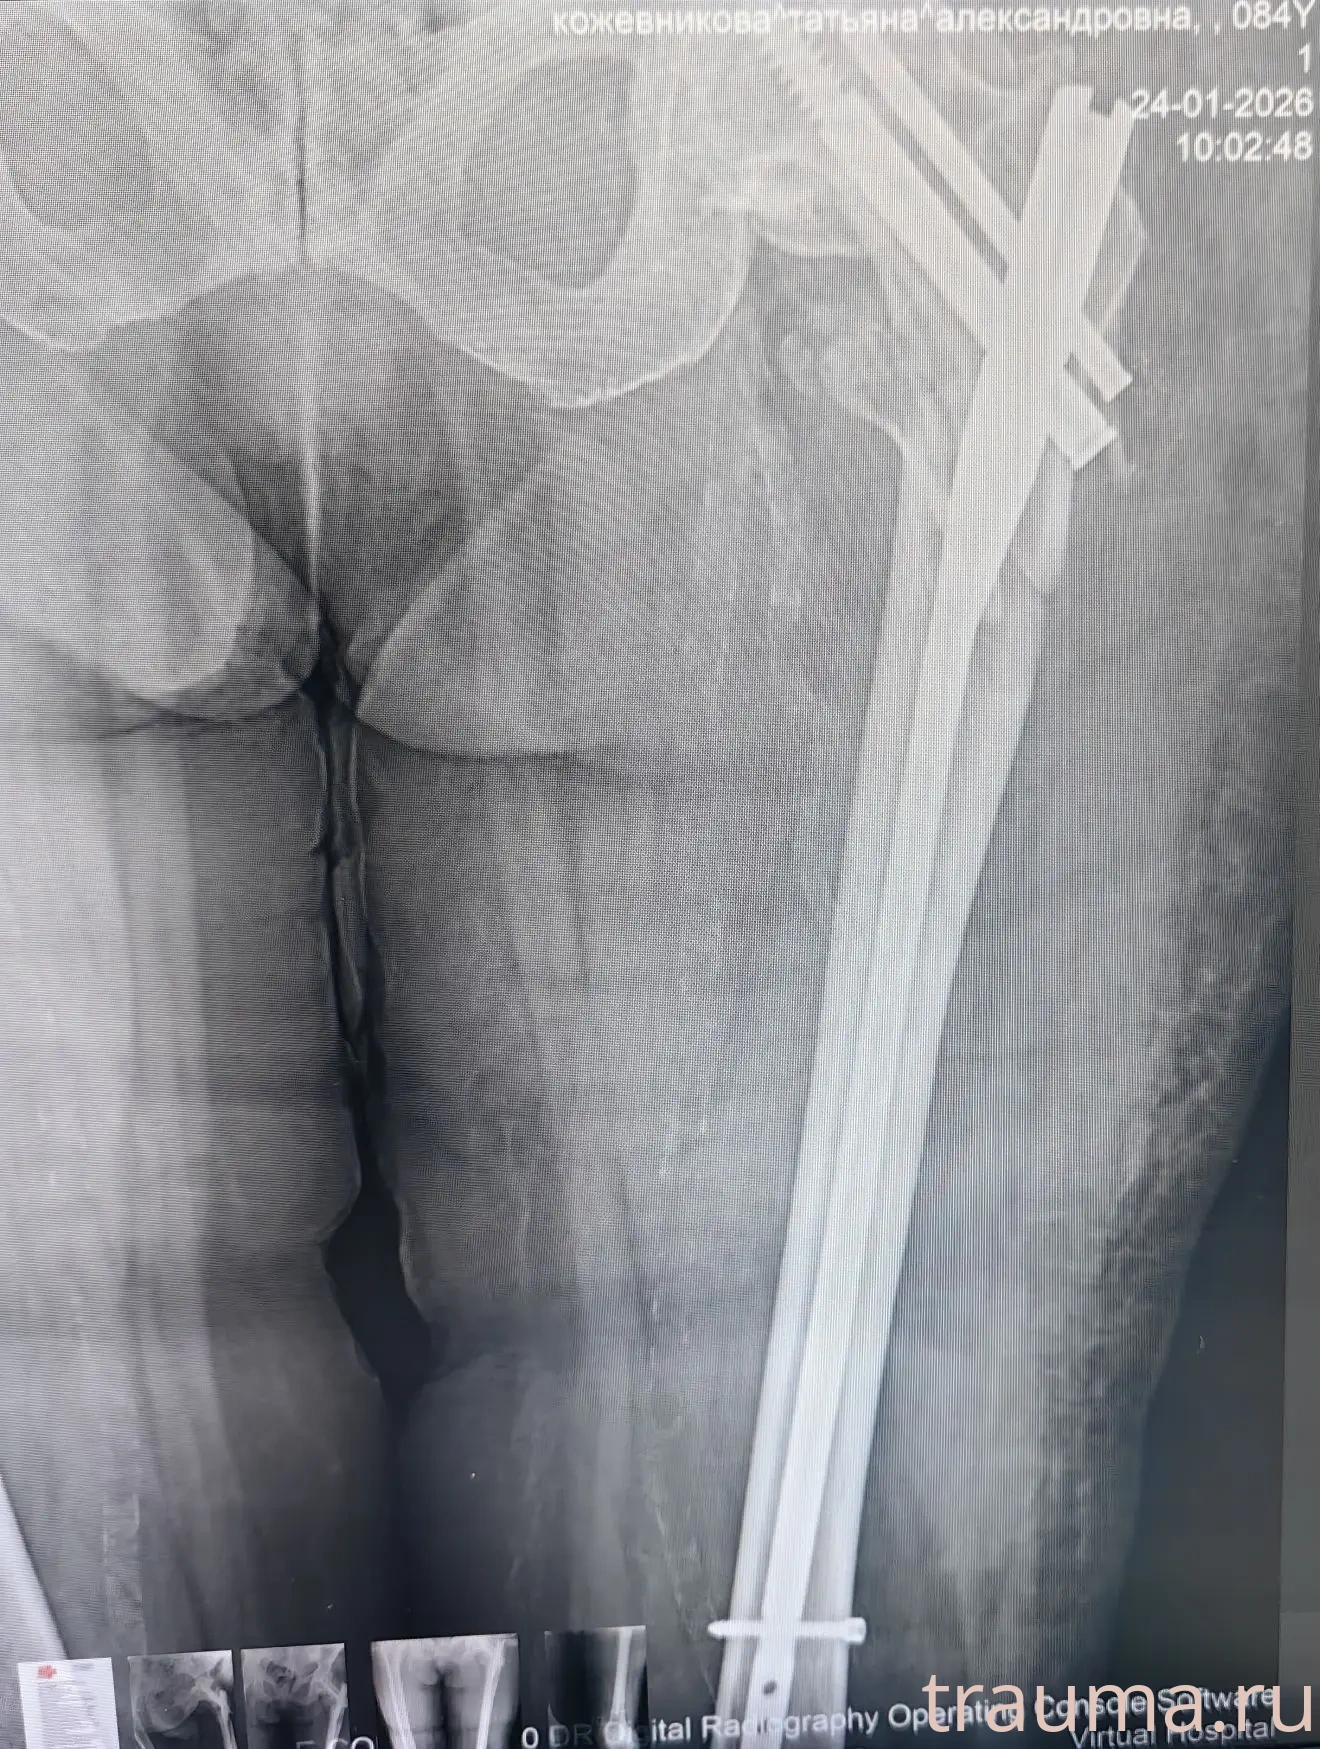

Рентгенограммы

24.01.2026

Рентген на дому: по вашему адресу приезжает врач-рентгенолог, травматолог-ортопед с мобильным рентгеновским аппаратом, проводит диагностику травмы или заболевания, делает необходимые рентгенограммы, дает рекомендации по дальнейшему лечению. Получить качественные снимки в домашних условиях возможно благодаря уникальной методике, разработанной МосРентген Центром для института  Склифосовского